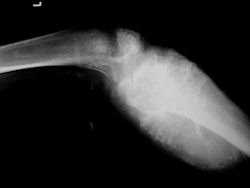

Gross Pathology: Osteosarcoma of Proximal Humerus

- originates from metaphysis of the proximal humerus, extends into surrounding soft tissues

- large soft tissue component that is crossing the glenohumeral joint

- was removed via an extra-articular resection, including scapula (Tikhoff-Linberg resection)